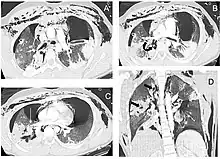

Rapid diagnosis and treatment are important in the care of TBI;[6] if the injury is not diagnosed shortly after the injury, the risk of complications is higher.[11] Bronchoscopy is the most effective method to diagnose, locate, and determine the severity of TBI,[6][10] and it is usually the only method that allows a definitive diagnosis.[23] Diagnosis with a flexible bronchoscope, which allows the injury to be visualized directly, is the fastest and most reliable technique.[8] In people with TBI, bronchoscopy may reveal that the airway is torn, or that the airways are blocked by blood, or that a bronchus has collapsed, obscuring more distal (lower) bronchi from view.[3]

Chest x-ray is the initial imaging technique used to diagnose TBI.[17] The film may not have any signs in an otherwise asymptomatic patient.[15] Indications of TBI seen on radiographs include deformity in the trachea or a defect in the tracheal wall.[17] Radiography may also show cervical emphysema, air in the tissues of the neck.[2] X-rays may also show accompanying injuries and signs such as fractures and subcutaneous emphysema.[2] If subcutaneous emphysema occurs and the hyoid bone appears in an X-ray to be sitting unusually high in the throat, it may be an indication that the trachea has been severed.[4] TBI is also suspected if an endotracheal tube appears in an X-ray to be out of place, or if its cuff appears to be more full than normal or to protrude through a tear in the airway.[17] If a bronchus is torn all the way around, the lung may collapse outward toward the chest wall (rather than inward, as it usually does in pneumothorax) because it loses the attachment to the bronchus which normally holds it toward the center.[6] In a person lying face-up, the lung collapses toward the diaphragm and the back.[23] This sign, described in 1969, is called fallen lung sign and is pathognomonic of TBI (that is, it is diagnostic for TBI because it does not occur in other conditions); however it occurs only rarely.[6] In as many as one in five cases, people with blunt trauma and TBI have no signs of the injury on chest X-ray.[23] CT scanning detects over 90% of TBI resulting from blunt trauma,[3] but neither X-ray nor CT are a replacement for bronchoscopy.[6]